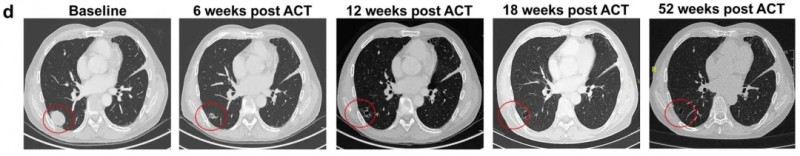

尤为值得关注的是1例生殖细胞肿瘤(GCT)患者的治疗历程:该患者初诊为混合型生殖细胞肿瘤,此前已接受5种化疗方案(含顺铂基础化疗、大剂量化疗联合自体干细胞移植HDCT/ASCT、吉西他滨+奥沙利铂+紫杉醇),并经历多次手术与放疗。在接受卡铂/依托泊苷大剂量化疗(HDCT)这一三线方案5年后,肿瘤晚期复发(含畸胎瘤与卵黄囊肿瘤成分);入组试验前,卵黄囊肿瘤成分再次复发,且首次出现肺转移,病情进展迅速——筛选至治疗(ACT)期间靶病灶总和增加37%。该患者肿瘤细胞中80%的CLDN6膜染色≥2+阳性,经淋巴细胞清除化疗(LD)后,接受单剂量CLDN6CAR-T细胞治疗。

治疗后疗效显著:治疗12周后PET-CT显示,患者肺部大块转移灶完全消失,达到代谢完全缓解(CR)(详见图a);肿瘤标志物甲胎蛋白(AFP)在治疗后7天内下降50%,且后续随访中持续受控(详见图b);CT扫描进一步证实肺部大块转移灶被完全清除,截至治疗后52周的最新复查,患者仍持续维持完全缓解(CR)状态(详见图d)。

▲图源“nature medicine”,版权归原作者所有,如无意中侵犯了知识产权,请联系我们删除